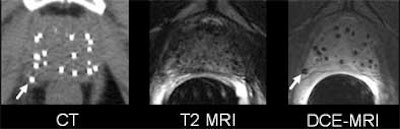

| Wayward brachytherapy seeds are well visualized, and better localized, in the contrast-enhanced MRI (the "D" in DCE-MRI stands for "dynamic," which is not necessary to optimize seed visualization, according to the authors). In patient 1 (top), a brachytherapy seed has migrated to the neurovascular bundle. In patient 2 (below), CE-MRI shows a seed that has lodged in a seminal vesicle, but cannot be localized in CT image at left. In patient 3 (bottom), the migration of seeds to the penile bulb is readily visualized on contrast-enhanced ("CE") MRI, lower right. All images courtesy of Dr. Klaus Kubin. |

According to the results, the T1-weighted GRE sequence localized 92% of the seeds overall (with per-patient accuracy ranging from 87%-99%), 14% of which were periprostatic. Twenty-five percent of the seeds were located in the neurovascular bundle, and 4% in the seminal vesicles.

T2-weighted MRI localized 78% of the seeds overall (range, 74%-86%), including 12% in periprostatic distribution, which was diagnosed more accurately on the T2 images. Twenty-four percent were found in the neurovascular bundle and 3% in the seminal vesicles, Kubin said.

CT won the sensitivity race, locating 97% of the seeds (range, 95%-100%). Two percent were suspected to be extraprostatic; however, the group was unable to assign the seeds to specific periprostatic structures.

The group concluded that T1- and T2-weighted MR were both more accurate for postbrachytherapy seed distribution than CT.

"The main idea is that the prostate takes up contrast media in general, not only the cancer, so if you wait long enough (up to 11 minutes after injecting contrast) the whole prostate is contrast enhanced," Bloch said. "But the seeds, of course, you see as voids because there is no contrast uptake. So if you use high-spatial-resolution MRI, no matter if it’s T2- or T1-weighted contrast enhanced, you see very nicely the prostate, the prostate capsule, and the neurovascular bundle, the penile bulb, and the rectal wall, but until now you couldn’t see the seeds."